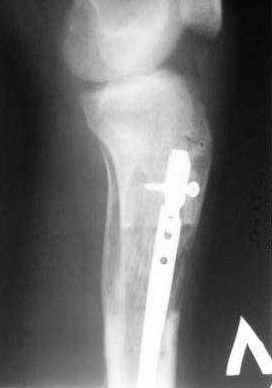

1 - рентгенограмма (прошу прощения за качество) при поступлении;

Произведено ПХО, acute shortening (5 см), фиксация стержневым аппаратом Hoffman.